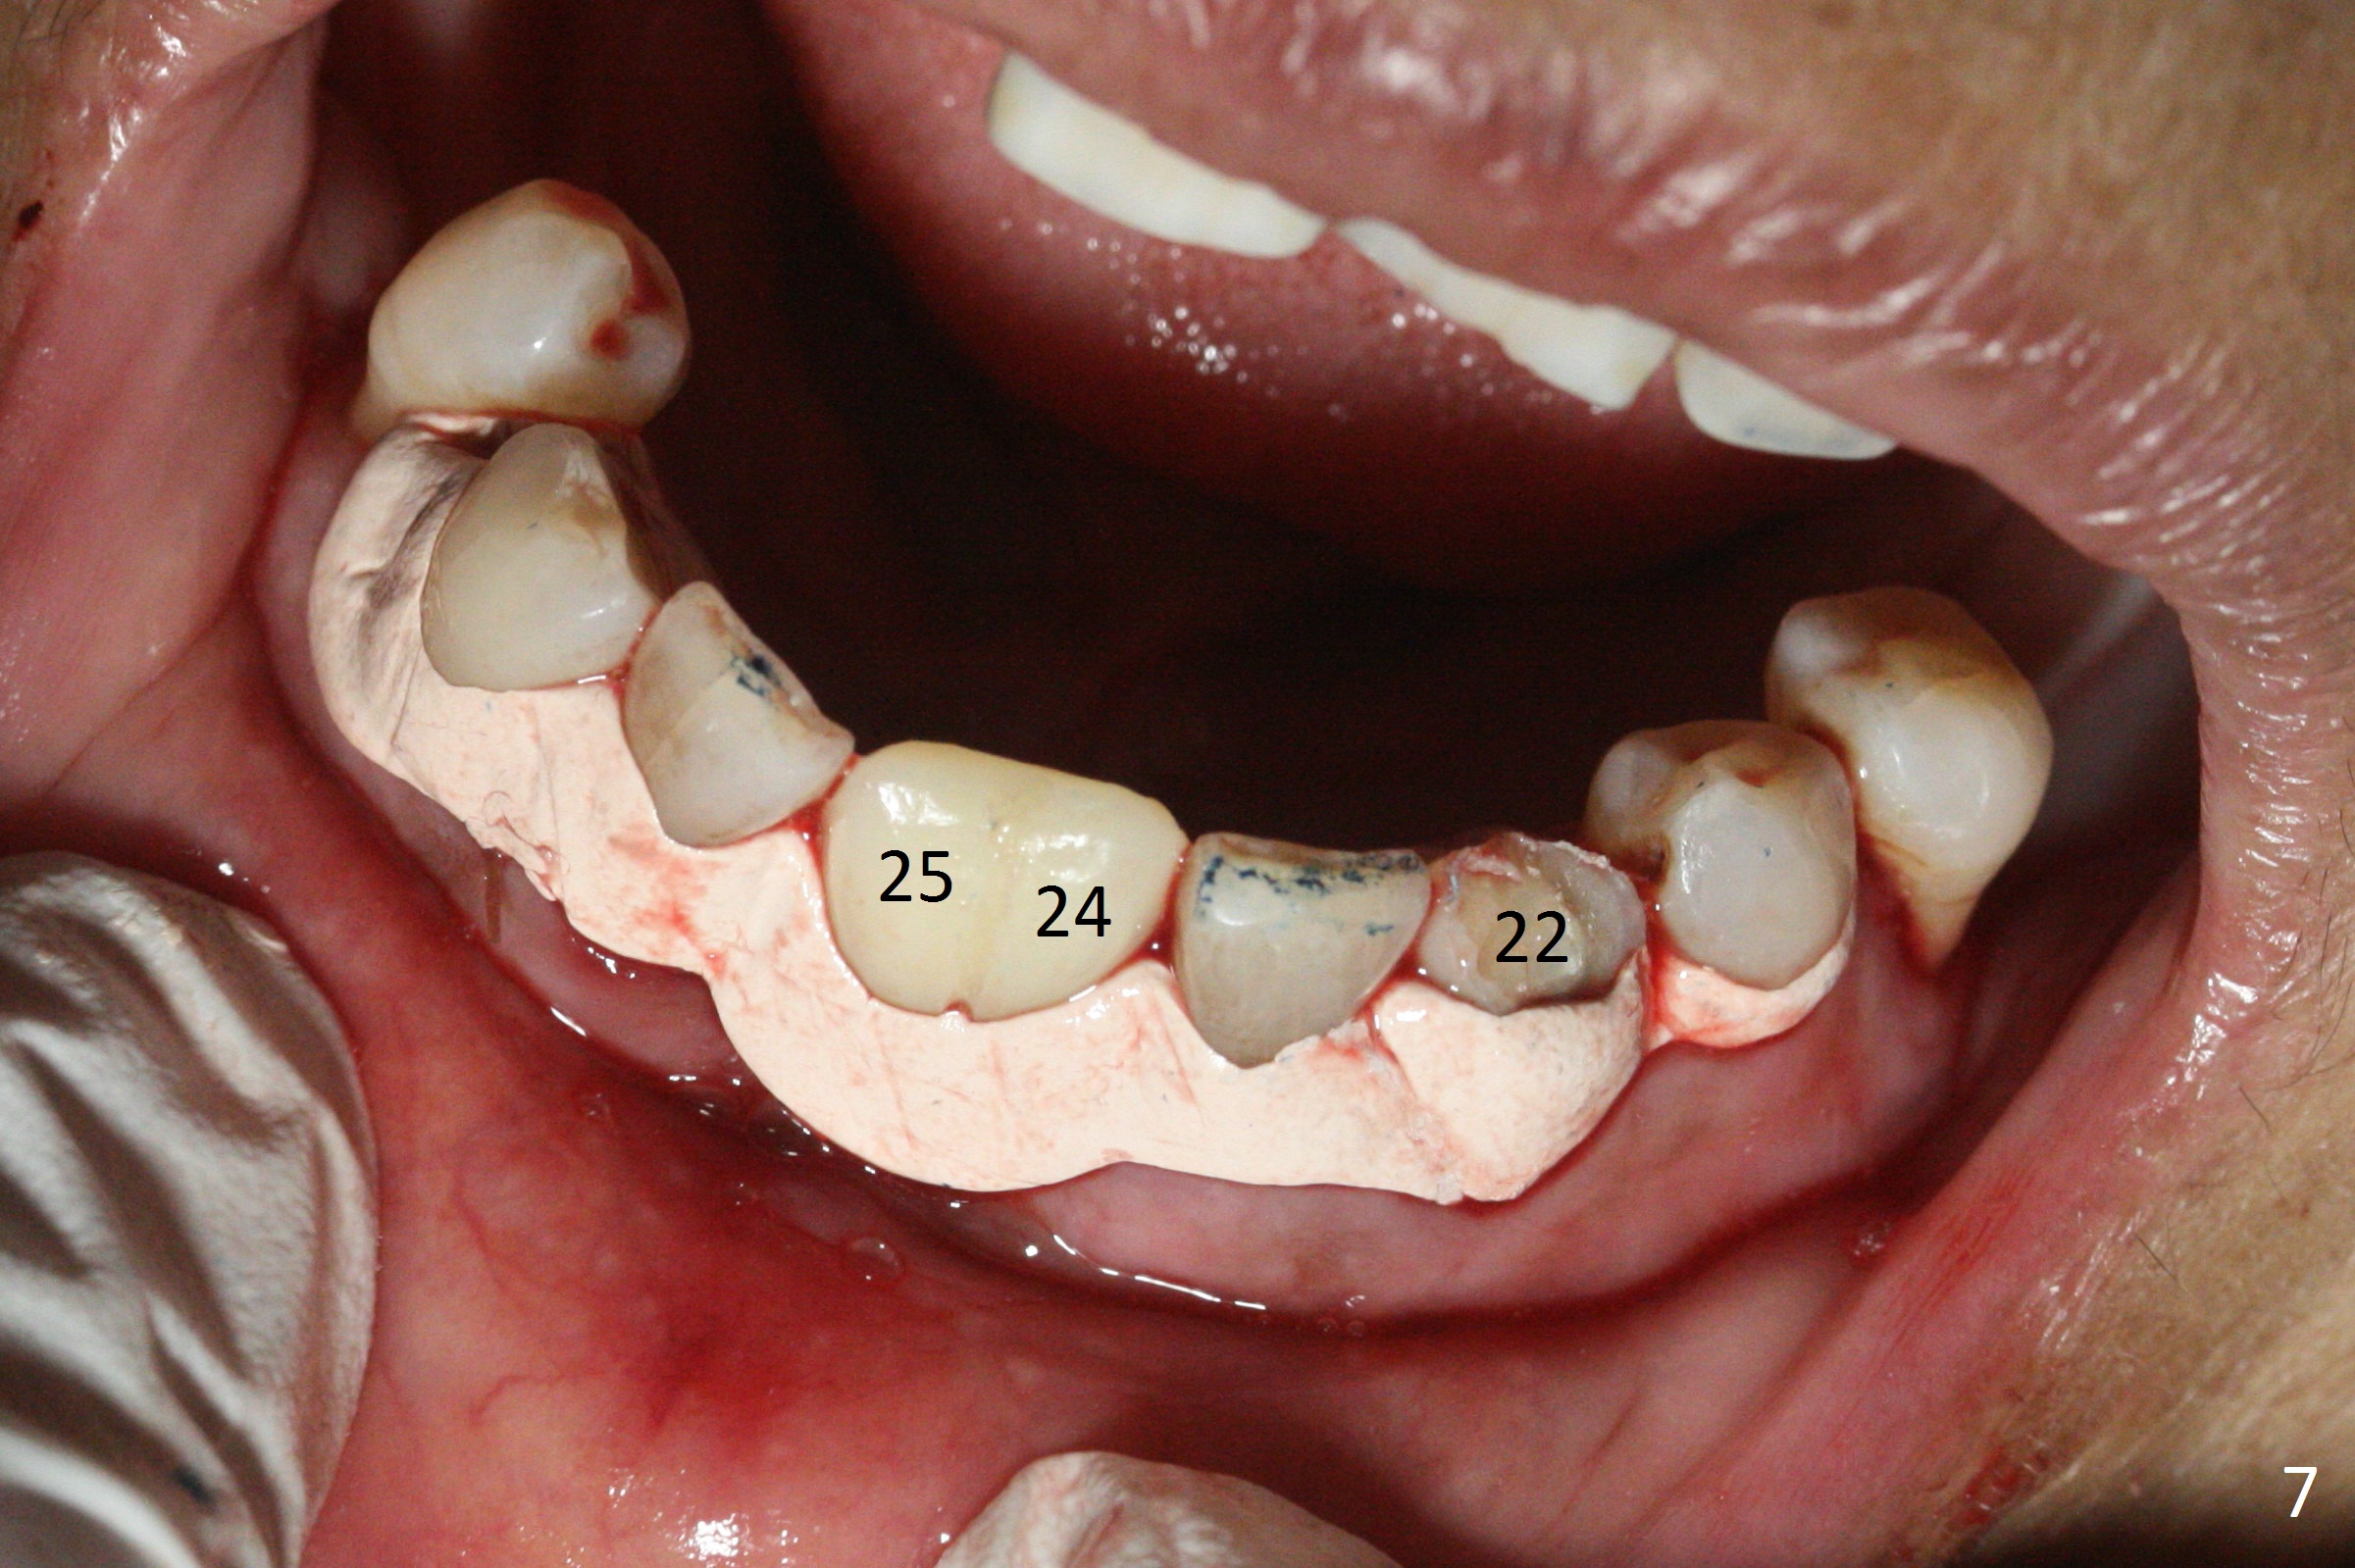

Before surgery, the patient reports that the tooth #25 has inclined to the position of #24 since the latter was extracted (Fig.1). After extraction of the tooth #25, there seems to be more bone vertically at the site of #24 than that of #25. Therefore the osteotomy is initiated at #24. The edentulous space is 9 mm mesiodistally, whereas the incisor width is 6 mm. The first pilot drill is fractured (1.2 mm). The latter is retrieved with incision. With better visibility, the initial osteotomy is found buccal. When a 3x14(2) mm dummy 1-piece implant is being placed partially, the buccal plate seems to be thin. A 2.5x14(4) mm 1-piece implant is placed instead with stability (Fig.2).

The depth of the osteotomy at #22 is 2-3 mm more than the expected implant length (Fig.2 with 2.7 mm drill in place). The implant at #22 (3.8x18 mm with insertion torque more than 50 Ncm) has clearance from the Incisive Canal and Mental Loop (Fig.3 red dashed line). Allograft with Osteogen is placed around the implants (Fig.4 *) in addition to Osteogen plug (cut in a thin layer) placed against the buccal wall of the socket at #22 (potential leakage). After suturing (Fig.5) and provisional cementation (Fig.6), periodontal dressing is applied (Fig.7). The implants seem to be ready for impression 4 months postop (Fig.8).